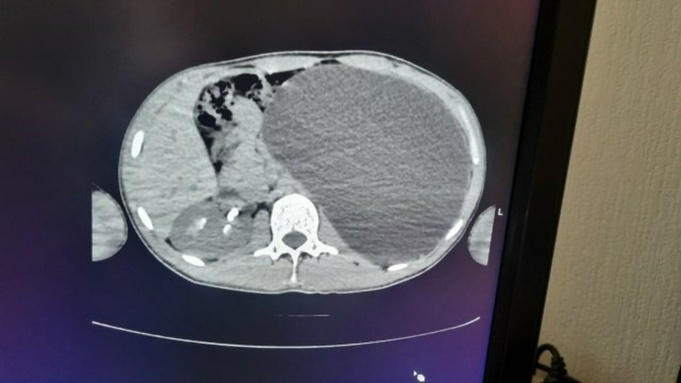

Снимок огромной почки / Фото: Минздрав Новосибирской области

По информации медиков, пораженный орган увеличился до размеров пятилитровой емкости и занимал практически всю брюшную полость. Врачи отмечают, что такое состояние представляло серьезную угрозу: при ударе могла произойти внутренняя разрывная травма с тяжелыми последствиями.